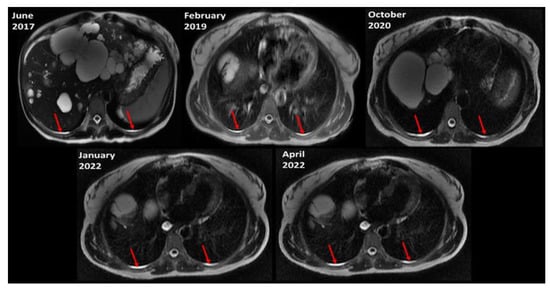

For 39 (70%) of all ADPKD subjects with pleural effusion, follow-up MRI was available ranging from 1.9 to 10.6 (mean = 5) years with a range of 2 to 7 scans (mean = 3.3) per subject. In these 39 ADPKD subjects with pleural effusions who had multiple MRIs, pleural effusion was identified on all follow-up MRIs in 35 of 39 (90%) (Figure 3). For the other 4 subjects, pleural effusion was identified on all but 1 follow-up scan in 2 and all but 2 follow-up scans in 2 subjects. For three ADPKD subjects with pleural effusion, CT was available within 2 months of the MRI. For all CTs the pleural effusion could be seen in retrospect, Figure 4, but was not mentioned in any of the CT reports.

Figure 3.

Pleural effusions (red arrows) are similar on successive axial T2-weighted MRI scans of the same subject over 5 years.